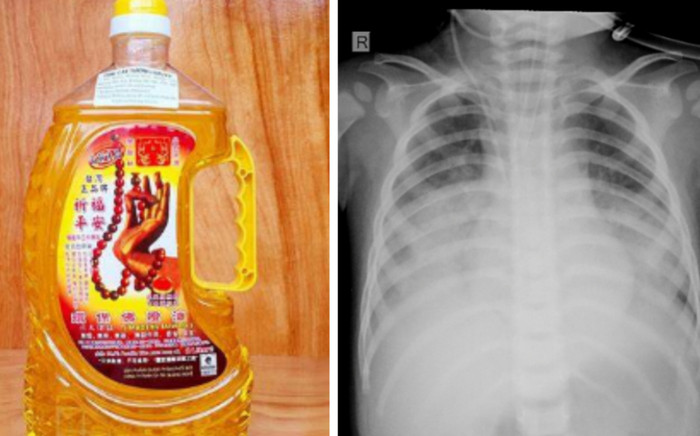

Theo Bệnh viện Sản Nhi Nghệ An, ngày 29/12, khoa Hồi sức tích cực chống độc của bệnh viện đã tiếp nhận một bệnh nhi bị ngộ độc do uống nhầm dầu thắp đèn dẫn đến viêm phổi nặng.

Loại dầu mà trẻ uống nhầm. (Ảnh: Bệnh viện).

Bệnh nhi T.N.H (15 tháng tuổi, ở Quỳnh Lưu) nhập viện trong tình trạng suy hô hấp, da tái, viêm phổi nặng. Người nhà bệnh nhi cho biết, trước khi vào viện 2h, trẻ uống nhầm dầu thắp đèn, sau uống trẻ bị sặc, ho, tím tái, khó thở.

Tại đây, trẻ nhanh chóng được các bác sĩ hỗ trợ hô hấp bằng thở máy áp lực cao cho trẻ, dùng kháng sinh phổ rộng. Hiện bệnh nhi vẫn đang trong tình trạng nguy kịch, cần theo dõi.

Theo BsCKII Nguyễn Hùng Mạnh – Trưởng khoa Hồi sức tích cực chống độc, Bệnh viện Sản Nhi Nghệ An cho biết, ngộ độc do uống nhầm hóa chất rất dễ xảy ra ở trẻ em. Các trường hợp uống xăng, dầu hỏa có thể gây viêm phổi bởi bệnh nhân dễ dàng hít phải hơi độc của hóa chất.